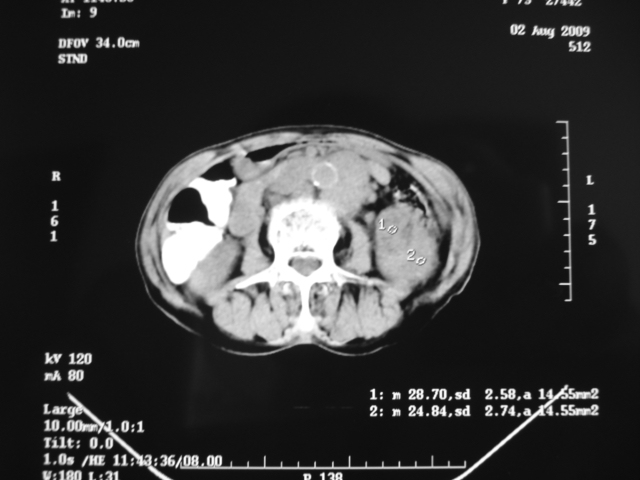

同事奶奶,73岁,腹痛一年,夜晚较重,潜血+++,拒绝增强,考虑左肾ca并腹膜后转移;请各位老师帮忙看看,谢谢!

左肾癌侵及输尿管上段,腹膜后多发淋巴结转移,脾脏钙化灶。至于潜血+++,要考虑消化道病变,本次ct片肠腔未见明显异常。

潜血+++是尿还是便?如果是便,则考虑肾癌侵犯降结肠可能。

1)考虑左肾癌侵犯肾盂并腹膜后淋巴结转移。2)脾脏钙化灶。